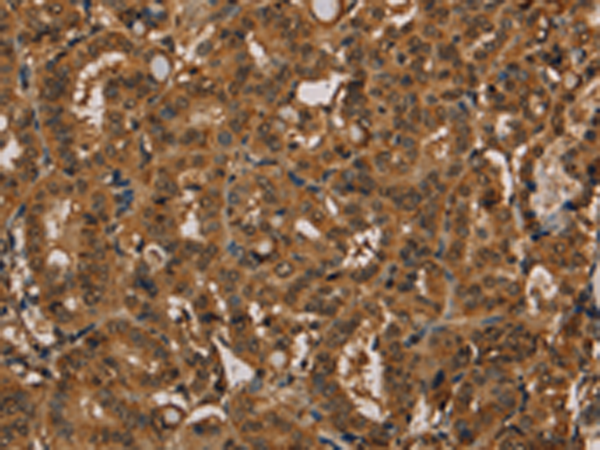

分类: 科研抗体货号: P08443别名:应用: IHC反应种属: Human, Mouse, Rat